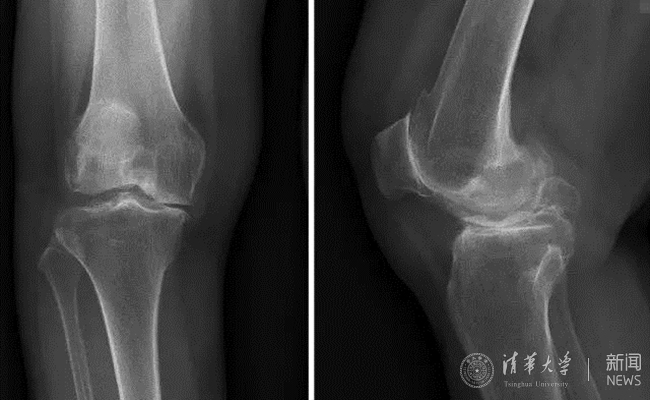

69岁的顾女士,已经有10年的右膝关节骨性关节炎病史,尝试了所有保守治疗后,膝关节疼痛未得到有效缓解,严重影响了生活。经介绍,患者找到北京清华长庚医院骨科关节中心主任蔡谞教授,希望进行膝关节置换手术。

患者术前膝关节正侧位平片。